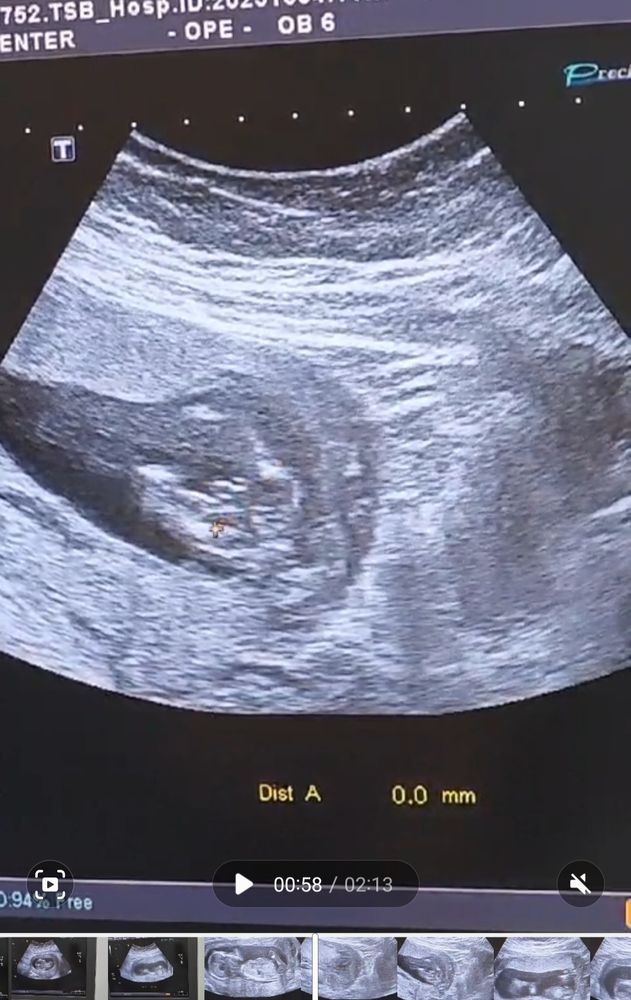

Девочки всем привет ❤️Срок 13.1 сказали мальчик,но я не уверена,фото приложила,вы что думаете?

На таком сроке пол в этом ракурсе не смотрят, смотрят в профиль по углу наклона бугорка. Со стороны попы смотрят позже, когда сформируются половые органы.

На таком сроке половой бугорок у обоих полов.Там смотрят угол наклона и "полосы".по фото непонятно

Юля, если я все верно понимаю, у автора на снимке жо. Вид снизу.

Trish, так и у нас вид с попы, видна сама попа , ножки,и чётко половой орган😅 а на снимке честно не пойму где что.🙈